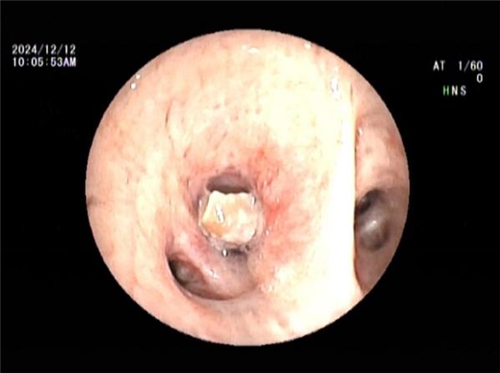

王海龙主任迅速组织团队对孟某展开全面综合评估,结合患者症状及各项检查结果,高度怀疑其患有吸入性气管异物并由此引发阻塞性肺炎。在与孟某及其家属进行充分且细致的沟通交流后,王海龙主任决定亲自为患者实施电子支气管镜检查。在支气管镜深入探查过程中,清晰可见患者右中叶支气管被一异物牢牢阻塞管腔。此异物表面光滑,质地极为脆弱,不仅易碎,还容易软化变形,这一系列棘手问题使得异物取出难度呈指数级增加。手术过程中,任何细微的失误都可能导致异物掉落至气管深部,从而引发更为严重且复杂的后果。但王海龙主任凭借其精湛高超的医术与沉稳冷静的临场应变能力,运用异物钳小心翼翼地进行操作,经过多次精准尝试,最终成功取出一枚长径约 1cm 的异物。术后,孟某的呼吸即刻恢复通畅,经过 5 天系统且精心的治疗,咳嗽、咳痰症状显著缓解,胸闷、气促等不适症状全然消失,肺部感染病灶也得到明显吸收。经确认,此次引发孟某一系列病痛的 “罪魁祸首” 竟是一粒花生米。